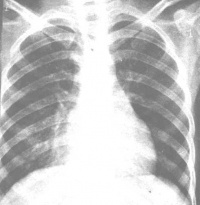

2.X线检查

X线形态与病情、病期有密切关系。肺纹理增厚、模糊为腺病毒肺炎的早期表现。肺部实变多在发病第3~5天开始出现,可有大小不等的片状病灶或融合性病灶,以两肺下野及右上肺多见。发病后6~11天,其病灶密度随病情发展而增高,病变也增多,分布较广,互相融合。与大叶肺炎不同之处是,本病的病变不局限于某个肺叶。病变吸收大多数在第8~14天以后。有时若病变继续增多、病情增重,应疑有混合感染。肺气肿颇为多见,早期及极期无明显差异,为双侧弥漫性肺气肿或病灶周围性肺气肿。1/6病例可有胸膜改变,多在极期出现胸膜反应,或有积液。

应根据流行情况,结合临床进行诊断。典型婴幼儿腺病毒肺炎早期与一般细菌性肺炎不同之处为:①大多数病例起病时或起病不久即有持续性高热,经抗生素治疗无效;②自第3~6病日出现嗜睡、萎靡等神经症状,嗜睡有时与烦躁交替出现,面色苍白发灰,肝肿大显著,以后易见心力衰竭、惊厥等合并症。上述症状提示腺病毒肺炎不但涉及呼吸道,其他系统也受影响;③肺部体征出现较迟,一般在第3~5病日以后方出现湿性罗音,病变面积逐渐增大,易有叩诊浊音及呼吸音减低,喘憋于发病第二周日渐严重;④白细胞总数较低,绝大多数病儿不超过12×109/L(12000/mm3),中性粒细胞不超过70%,中性粒细胞的碱性磷酸酶及四唑氮蓝染色较化脓性细菌感染时数值明显低下,但如并发化脓性细菌感染则又上升;⑤X线检查肺部可有较大片状阴影,以左下为最多见。总之,在此病流行季节遇有婴幼儿发生较严重的肺炎,且X线和血象也比较符合时,即可作出初步诊断。有条件的单位,可进行病毒的快速诊断。目前可进行免疫荧光技术(间接法较直接法更为适用)、酶联免疫吸附试验及特异性IgM测定,唯此三种方法均不能对腺病毒进行分型,是其不足之处。而常规咽拭子病毒分离及双份血清抗体检查,只适用于实验室作为回顾诊断。